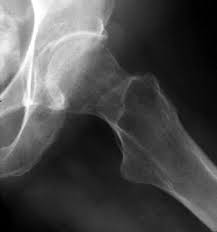

Un gruppo di ricerca dell'Istituto Telethon di Pozzuoli (Napoli) ha scoperto che la crescita delle ossa dopo la nascita è sostenuta da un preciso meccanismo. In pratica si tratta di un fenomeno noto come autofagia che regola l'accrescimento del tessuto osseo dopo la nascita. L'autofagia, in particolare stando a questa ricerca, viene determinata da uno specifico fattore di crescita, l'fgf 18.

I ricercatori hanno osservato come nei topi privi di questo fattore di crescita l'autofagia non si realizza correttamente, il che dà luogo a svariate patologie dell'apparato scheletrico quali ad esempio l'acondroplasia, ovvero alla forma più comune e diffusa di nanismo.

In pratica grazie all'autofagia che si svolge in tutti i tessuti dell'organismo, le cellule riescono ad eliminarsi vicendevolmente tramite degradazione secondo un meccanismo regolato da una serie di fattori bio-chimici, il cui disturbo può portare a molte patologie dell'apparato scheletrico.